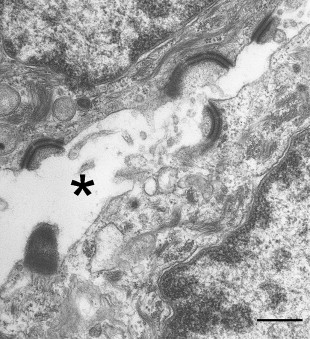

Light microscopy of skin revealed extensive suprabasal clefting with some spongiosis and acantholysis ( Fig. 1 C). These changes extended into hair follicles and eccrine ducts. Ultrastructurally, there was evidence for detachment of keratin intermediate filaments from the inner plaques of desmosomes in all layers of the epidermis ( Fig. 2 ). The number and size of the desmosomes appeared normal and both inner and outer plaques were clearly discernible. In contrast to many other autosomal-recessive blistering genodermatoses, however, immunolabeling of skin with antibodies to a panel of desmosomal and hemidesmosomal proteins was not helpful in establishing a candidate gene for mutations. Notably, all antibodies showed normal intensity staining although the pattern of staining for several desmosomal proteins was more punctate: This was the case for desmoplakin (DSP), plakoglobin, plakophilins, desmogleins, and desmocollins. In addition, labeling with keratin antibodies showed a condensed perinuclear staining, rather than a diffuse cytoplasmic pattern. The skin biopsy clue that led to the DSP gene ( DSP ) as the candidate gene was the ultrastructural observation that keratin filaments failed to connect properly to the inner dense plaques of desmosomes, a finding that had been observed previously in DSP knockout mice and in patients with nonsense/missense combinations of mutations in DSP , resulting in skin fragility–woolly hair syndrome (MIM607655).